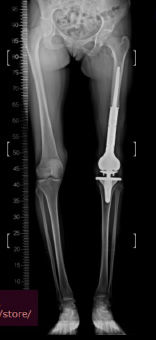

Klasik osteosarkomun cerrahi tedavisi, tümör ve tümör dokusu ile temas etmiş tüm bölgelerin, üzerinde yeterli kalınlıkta sağlıklı doku örtüsü bırakılarak, tümöre dokunulmadan çıkartılmasıdır. Kemoterapi, tümörü küçülterek çıkartılmasını kolaylaştırmak, bölgesel tekrar (lokal nüks) riskini azaltmak ve sistemik yayılmayı (metastaz) engellemek için ameliyat öncesi (neodjuvan) ve ameliyat sonrası (adjuvan) mutlaka uygulanmalıdır. Neoadjuvan kemoterapi ile mikrometastazların önüne geçmeye çalışılır.